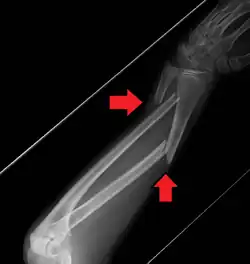

A fracture of the forearm can be classified as to whether it involves only the ulna (ulnar fracture), only the radius (radius fracture), or both radioulnar fracture.

For treatment of children with torus fractures of the forearm splinting appears to work better than casting.[7] Genetically determined disorders like hereditary multiple exostoses can lead to hand and forearm deformities. Hereditary multiple exostoses is due growth disturbance of the epiphyses of the radius and ulna, the two bones of the forearm.[8]